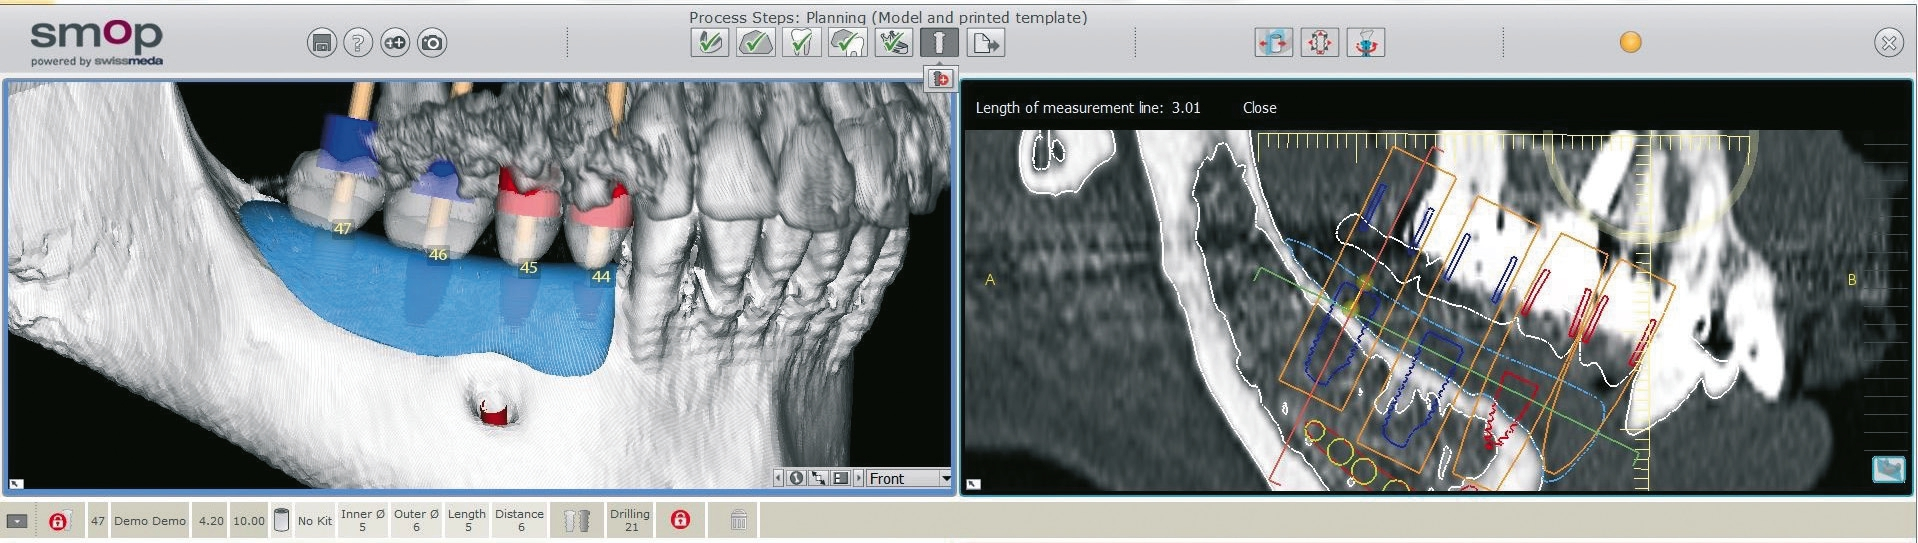

Eine 42 Jahre alte Frau stellte sich mit dem Wunsch nach einer festsitzenden prothetischen Versorgung im Unterkiefer vor. Die Voruntersuchung und die Röntgenaufnahmen zeigten eine Atrophie des Unterkiefers und damit ein für das Setzen von Implantaten eingeschränktes ortsständiges Knochenangebot (Abb. 1 und 2). Der Patientin wurden verschiedene Behandlungsoptionen für ein zweizeitiges GBR-Verfahren vorgestellt, um eine ausreichende Kammbreite für die anschließende Implantatbehandlung zu erhalten. Die Patientin lehnte ein Augmentationsverfahren mit autologem Knochentransplantat ab. Der vereinbarte Behandlungsplan beinhaltete letztendlich einen Knochenaufbau mit einem individuell konstruierten, gefriergetrockneten CADCAM-Allograft (maxgraft® bonebuilder, botiss biomaterials GmbH) und die anschließende Implantation von Straumann® BLX Roxolid® SLActive® Implantaten.

Der Lappen wurde reponiert und mit nicht resorbierbarem Nahtfaden der Stärke 4.0 adaptiert. Um einen spannungsfreien Wundverschluss zu erreichen, wurde apikal eine laterale Matratzennaht gesetzt. Die Nähte wurden nach 14 Tagen entfernt. Nach sechs Monaten komplikationsfreier Wund- und Einheilung kam die Patientin zur Implantatbehandlung erneut in die Praxis (Abb. 6 und 7). Beim Re-Entry wurden die Befestigungsschrauben entfernt, und es wurde eine Knochenkernbiopsie für die histologische Analyse entnommen (Abb. 8 und 9). Die histologische Untersuchung der mit Hämatoxylin-Eosin eingefärbten Schnittpräparate der Probe zeigte den laufenden Umbauprozess des FDBA-Blocks. Die histologische Aufnahme (Abb. 10) zeigte neu gebildeten Geflechtknochen (WB) in engem Kontakt mit dem Allograftmaterial (*) und umgeben von Bindegewebe (CT) und belegte die durch das Allograftmaterial vermittelte Knochenregeneration. Nach Bestimmung der geeigneten Implantatpositionen wurden in regio 47, 46 und 44 drei Bone Level Implantate Straumann® BLX Roxolid® SLActive ® mit einem Durchmesser von 4,5 mm und einer Länge von 10 mm gesetzt (Abb. 11 bis 14). Die Implantate wurden mit RB Verschlusskappen verschlossen, der Wundverschluss erfolgte mit Nahtmaterial der Stärke 4.0 (Abb. 15 und 16).